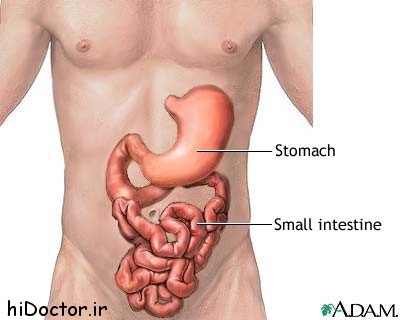

عکس داخل شکم انسان. در این همان طور که مشخص است شکم حالت بیضی شکل پیداکرده و این بیضی که کناره های شکم کشیده شده است. تعداد سلول های بدن انسان حدود ۳۷ ۲ تریلیون تخمین زده شده اند. Abdomen که در زبان عامه به غلط به آن دل نیز می گویند در آناتومی به قسمتی از تنه گفته می شود که مابین دیافراگم از بالا و سطح فوقانی لگن خاصره از پایین قرار دارد. ربات دیدنی ربات انساننمای چینی به صورت یک دختر جوان ساخته شده و جیا جیا نامگذاری شده است این ربات طوری برنامهریزی شده که میتواند صحبت کند و احساسات خود را از طریق تغییرات در چهره حالات.

شکل دوم شکم مادری را نشان می دهد که جنین دختر دارد. وحشت مادر از عکس سونوگرافی جنین داخل شکمش عکس. تصاویر جالب از داخل مغز و نخاع انسان آخرین نیوز. بدن انسان کل ساختار انسان است که سر گردن تنه سینه و شکم دو بازو و دست ها و دو ساق پا و پاها را شامل می شود.